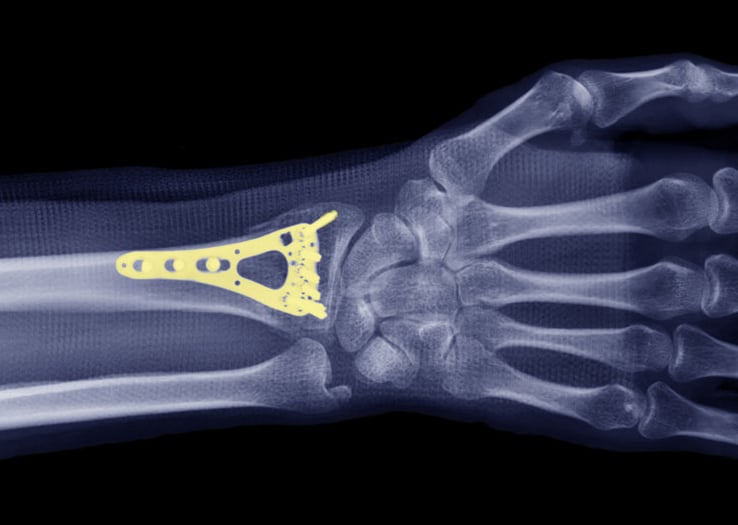

Distal radius fractures require surgery to repair when the fracture pieces are unstable (won’t stay in place) or involve the wrist joint surface. We perform a regional block to numb the arm and then make a small incision at the wrist to restore the alignment of the distal radius and hold the pieces in place with a metal plate and screws.

X-ray of a wrist with plating to repair a distal radius fracture